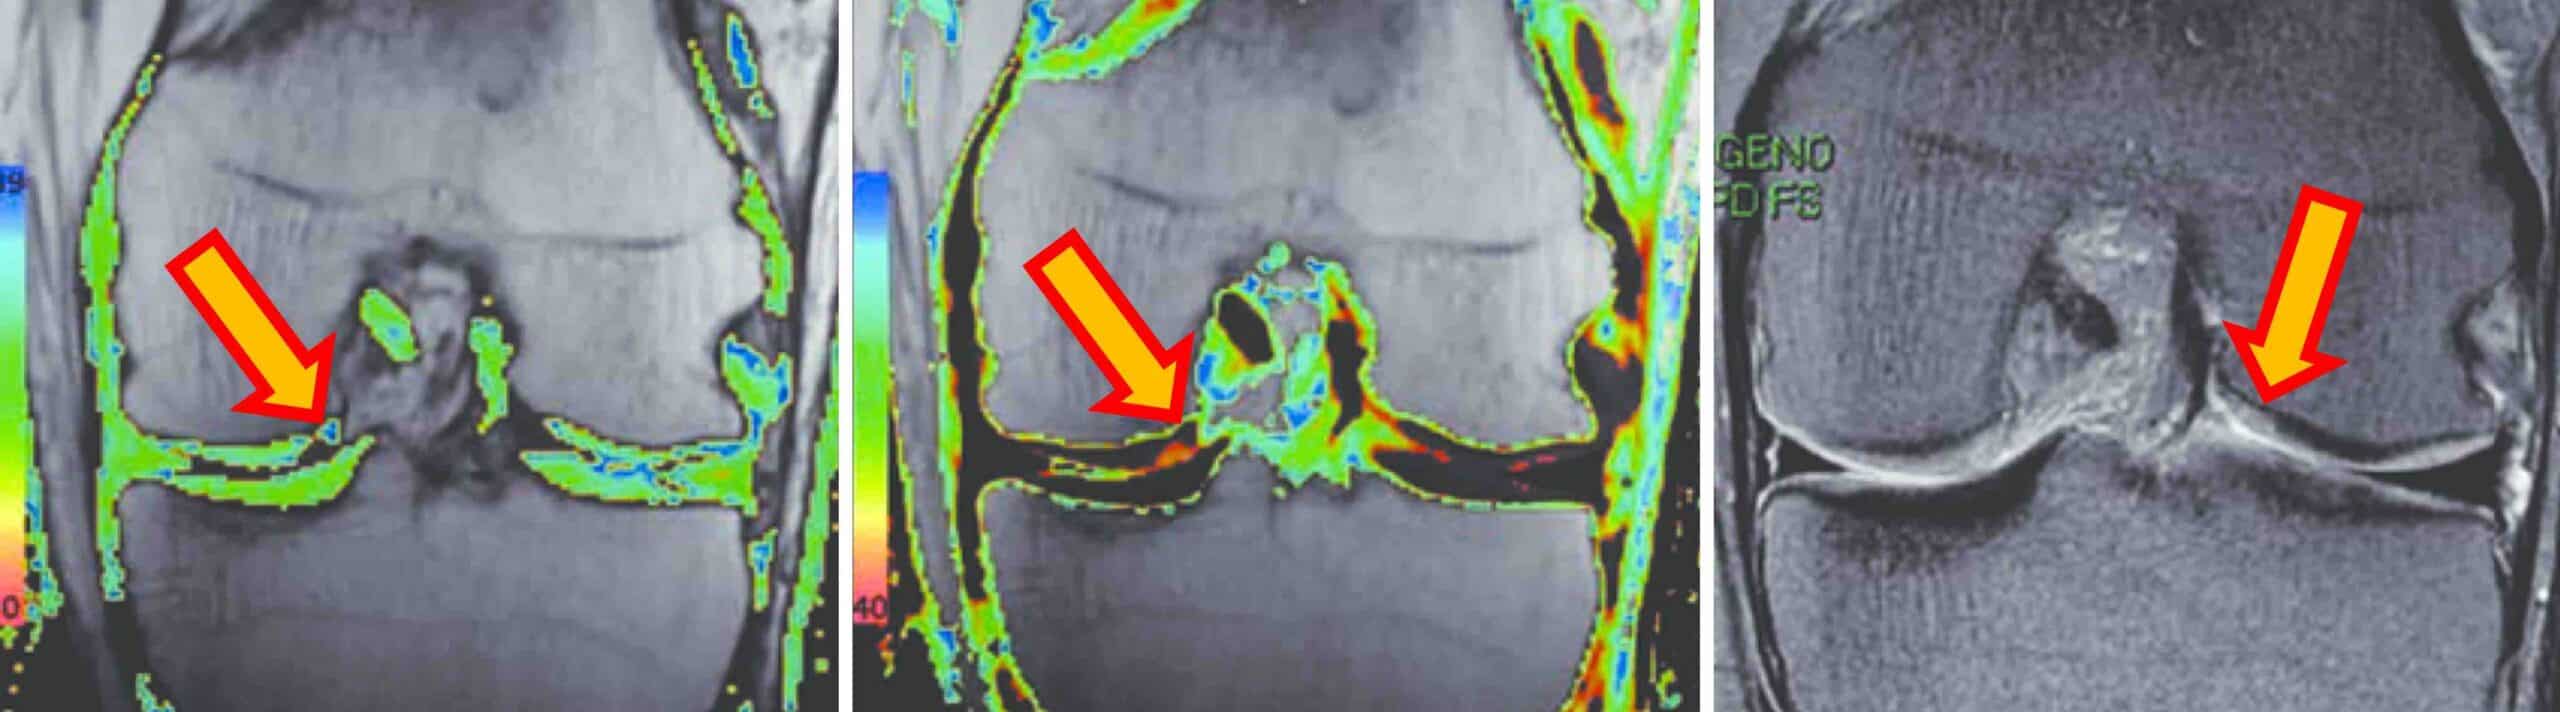

O método mais utilizado para se fazer a condrometria do joelho é através do exame de ressonância magnética. Essa técnica é também conhecida como ressonância condral. Sequências específicas do exame de ressonância magnética mapeiam a cartilagem do joelho e detectam alterações estruturais microscópicas antes mesmo de aparecerem nas sequências convencionais. A condrometria detecta alterações fisiológicas na cartilagem relacionadas à sua composição bioquímica. A partir dos dados da condrometria o computador monta o cartigrama, que é a representação gráfica colorida da cartilagem do joelho. No cartigrama a cartilagem é mapeada com diferentes cores que evidenciam mudanças sutis na ultraestrutura condral.

A condrometria do joelho é realizada por meio de um equipamento de ressonância magnética de alta resolução. O paciente permanece deitado e o joelho é posicionado no aparelho de ressonância. Não há necessidade de contraste para se fazer a condrometria do joelho através da ressonância magnética. As imagens obtidas são processadas por softwares específicos que medem a espessura da cartilagem e geram o cartigrama, que é um mapa condral colorido mostrando as áreas de desgaste ou as alterações estruturais na cartilagem.